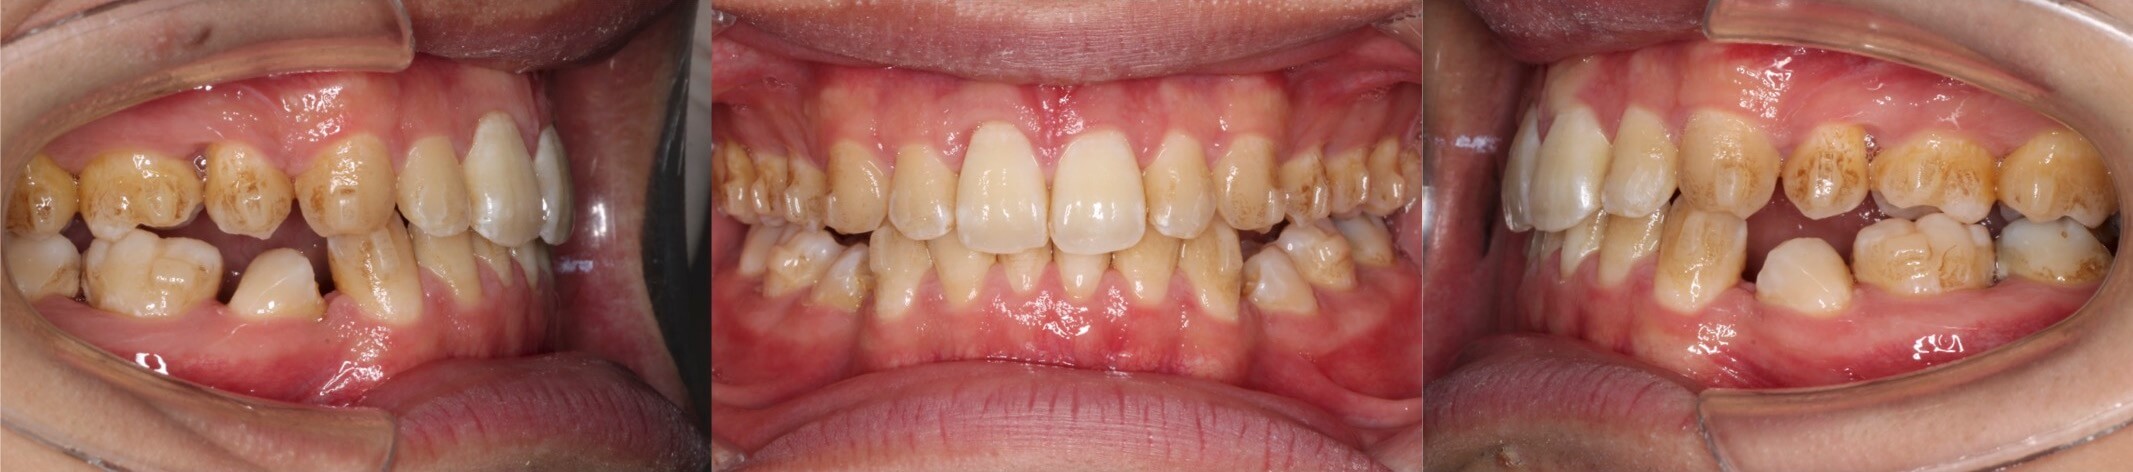

実際にマウスピース型矯正治療でボーイングエフェクトが発生したケースです。抜歯空隙に隣接歯が倒れ込み、前歯部では過蓋咬合、臼歯部では離開が起きています。

マウスピース型矯正装置のみでのリカバリーは困難と判断し、重度の臼歯傾斜が発生している下の歯列のみ唇側矯正装置でリカバリーを行いました。途中ワイヤーを2本使用することで、歯にモーメントを発生させ、無事ボーイングエフェクトが解消しました。リカバリーにかかった治療期間1年3か月と長期にわたりました。

<ボーイングエフェクトの発生>